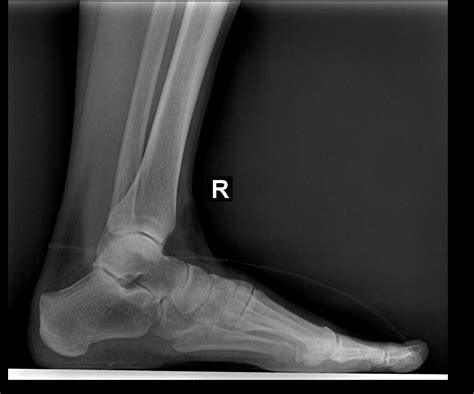

Lateral Ankle Xray

A Lateral Ankle Xray is a specific type of X-ray that provides a side view of the ankle. This view is particularly useful for assessing the alignment of the bones and identifying fractures or dislocations. The lateral view complements other views, such as the anteroposterior (AP) and mortise views, to give a comprehensive picture of the ankle's condition.

Interpreting a Lateral Ankle Xray requires a trained eye to identify key features and abnormalities. Some of the important aspects to look for include:

• Bone alignment: Ensuring that the bones are properly aligned and there are no signs of fractures or dislocations.

• Joint space: Assessing the width and uniformity of the joint space to detect any signs of arthritis or other joint issues.

• Soft tissue swelling: Identifying any swelling or inflammation around the ankle that may indicate an injury.

Radiologists and orthopedic specialists are trained to interpret these images and provide a detailed report of their findings. This report is then used to guide treatment decisions.

Some of the common findings on a Lateral Ankle Xray include:

• Fractures: Visible breaks in the bones, which may be simple or complex.

• Dislocations: Misalignment of the bones, often due to severe trauma.

• Osteoarthritis: Changes in the bone structure and joint space indicative of degenerative joint disease.

• Soft tissue swelling: Inflammation or edema around the ankle, which may be due to injury or infection.